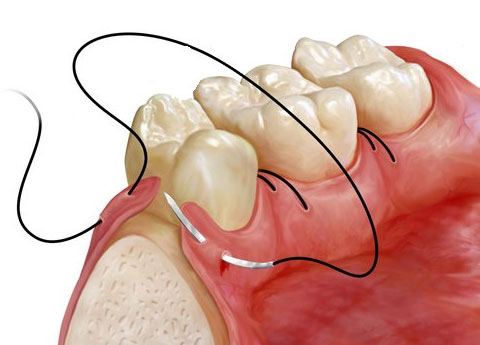

- Anestezie

- Incizie și decolarea lamboului

- Odontotomie (dacă este necesar)

- Extracția dintelui

- Sutură

- Control postoperator